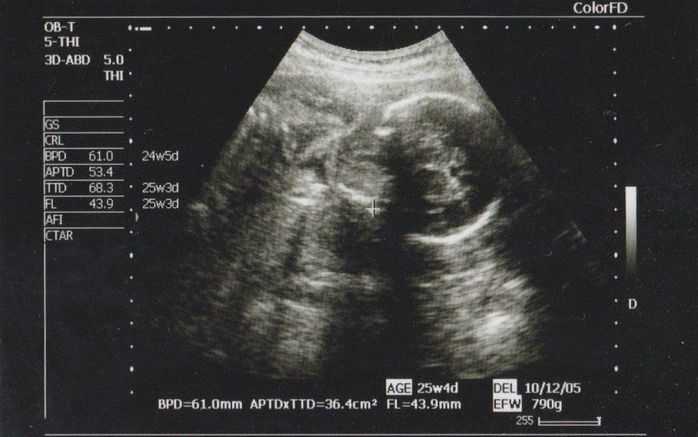

妊娠24週目のエコー写真

胎児は順調に大きくなり、この頃から全身が写らないくらいのサイズになっていました。帰国後初めての健診だったので、少しドキドキしていました。特に体調に変化はなかったものの、エコーで我が子を見るまでは、心からの安心はできませんでした。